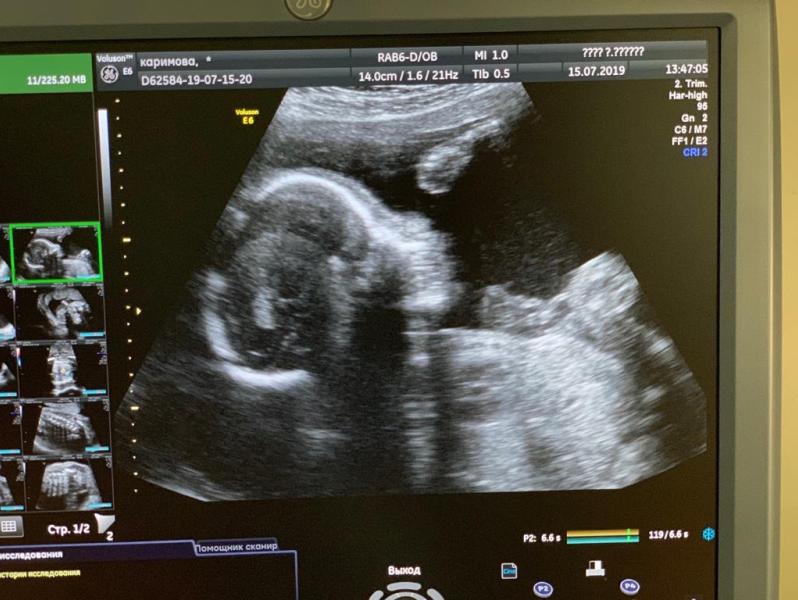

На третьем скрининг сказали что у малыша перевес (весит примерно 2000 гр), но в программах для беременных пишут что это норма. А меня посадили на диету, сказали малыш не перестанет набирать вес, то на кесарево пойду. Как вы считаете? Бывало ли у вас такое? Срок 33 недели

Я была на 31 неделе вес малыша был 2160, поставили крупный плод, сейчас на диете🥴, повторное узи сказали сделать в 38 недель, ждём

Я на 32-33 неделе была на 3 скрине. Он весил 2200. Тоже перевес. Родила на 41 неделе 3 день 51 см 3200 гр.

У нас такой же вес на 3 скрининге был,ничего не сказали ... Все в норме

Я тоже думаю что это нормально) но у малыша на узи прям щечки такие большие и складки 😅❤️